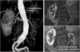

Atrophic kidney

Chronic kidney disease (CKD) is a type of kidney disease in which there is gradual loss of kidney function over a period of months to years. Initially there are generally no symptoms; later, symptoms may include leg swelling, feeling tired, vomiting, loss of appetite, and confusion. [Source: Wikipedia ]